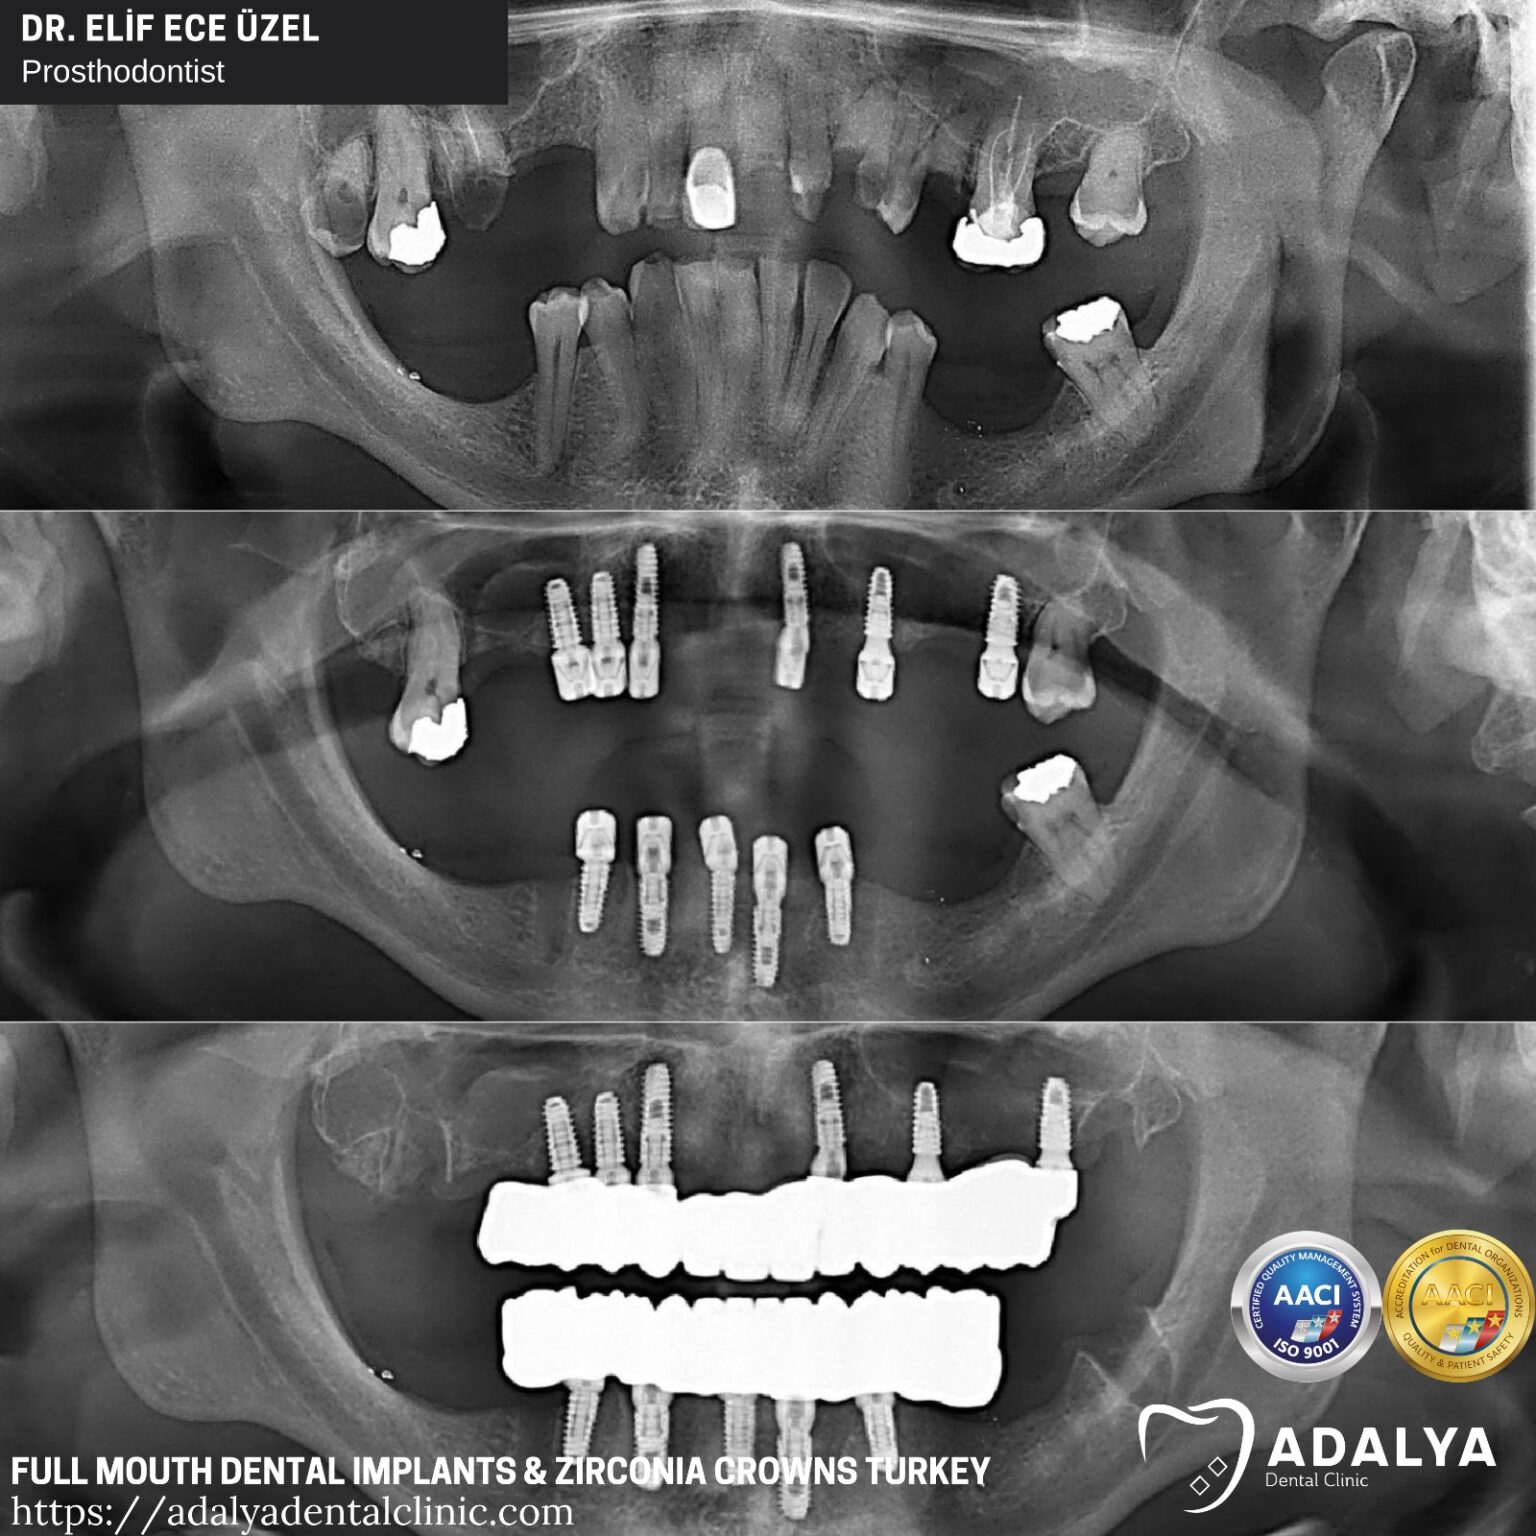

Full mouth dental implants in Turkey package deals make this reliable method of restoring the entire dental rows affordable for patients with total adentia Full mouth dental implants in Turkey package deals are priced between €2500 to €8000 As Care in Turkey, we offer full mouth dental implants package deals that seamlessly blend the high standards of treatment with the joys of a Turkish holiday

Full Mouth Dental Implants Turkey Package Deals Full Set Implants Cost. The cost of full mouth dental implants in Istanbul is not only competitive but also offers unparalleled value when one considers the expertise and the technology at play. How much are full mouth dental implant prices with Dental Clinic Turkey? Our Current Full Mouth Implant Packages, Benefits of Full Implants